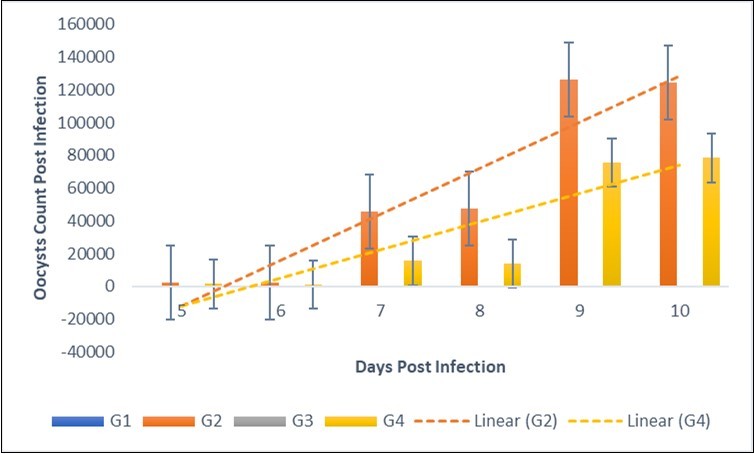

The Effect of NeemAzal® on Oocyst Count and Weight Gain (Efficacy Study) at a dose of 200mg/kg birds treated with NeemAzal® a statistically significant (P≤0.05) increase in weight gain was recorded among treated groups (Figure 1 & Figure 2). During the first 3 days of infection, there was no fecal output of oocysts. On day5 p.i., the output differed between NeemAzal® treated and non-treated chickens. In the latter, the number of excreted oocysts reached approximately 1.3×105 per gram feces (Figure 2).

Figure 1.Therapeutic effect of NeemAzal® on oocyst count of Broiler chicken infected with Eimeria tenella oocysts. G2=negative control (infected, not treated). G3=positive control (infected and treated with amprolium).